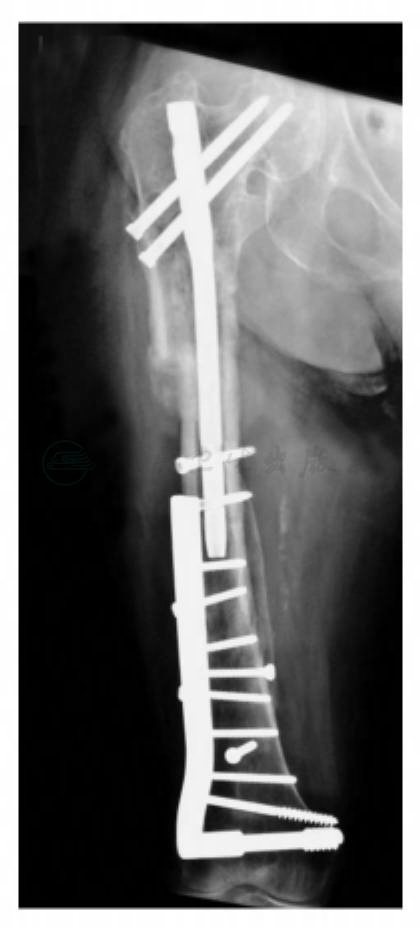

手术治疗的目的是避免长期卧床,尽快恢复肢体站立行走能力,避免长期卧床带来的并发症,减缓心肺功能退化的速率。但患者已经90岁高龄,基本原则是积极、慎重、简单有效。手术技巧:该患者原有两处内固定物,股骨髁上部位的DCS和股骨近端的“鹅头钉”。为减少手术创伤,DCS保留不动,但原有“鹅头钉”必须取出,计划采用股骨近端髓内钉,取出“鹅头钉”后其三翼钉部分可能在股骨头颈内留下空隙不利于新的拉力钉置入,有可能拉力钉把持不牢,但可以考虑采用双钉结构的内固定物。估计可能与股骨颈内的三翼钉角度有所不同,况且双钉打入后可以保证有一根固定质量较高,而且是转子下骨折,拉力钉主要起到锁钉作用,受力情况小于转子间骨折。术中采用“鹅头钉”专用取出器,顺利取出,打入股骨近端髓主钉时受到DCS近端皮质螺钉的限制,故将DCS近端皮质骨螺钉取出一枚,打入两枚股骨头颈内的锁钉,两枚拉力均较好,因为是转子下骨折,所以远端锁钉用了两枚。受到原骨折愈合后的髋内翻影响,其股骨头颈内的拉力钉位置不是十分理想,手术时间90分钟。术后没有发生各类并发症,术后1周下床不负重活动(图3)。

图3 术后X线片